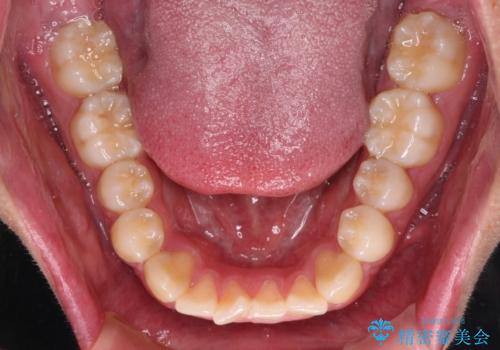

- 上下前歯の叢生を気にして来院された患者様です。

費用を抑え、期間もあまりかけずに治療をしたいとのことで、インビザライン・ライトを用いて矯正治療を行うこととしました。